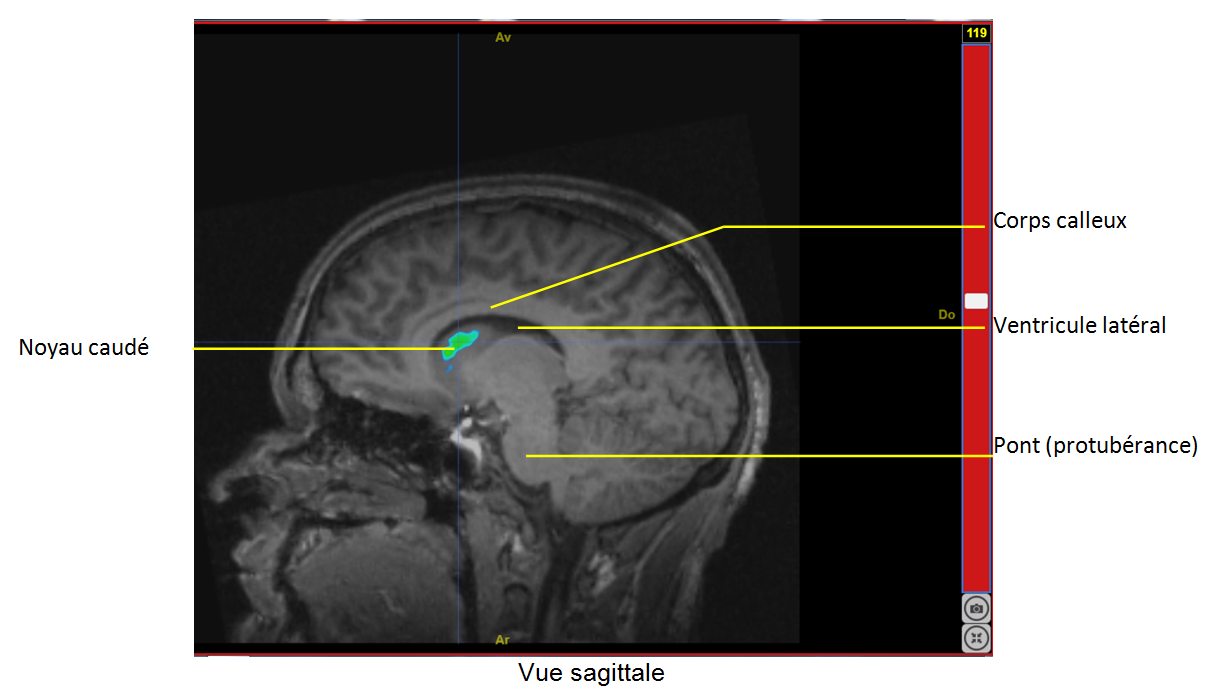

Capture Sagit